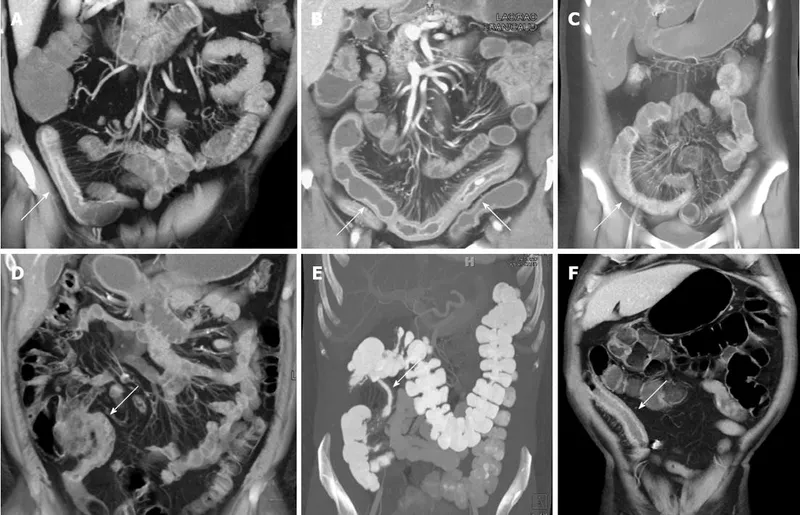

Cross-sectional imaging reveals transmural and extraintestinal disease features:

📌 Remember: COMB sign on CT - Comb-like mesenteric vessels, Obvious in active CD, Mesenteric fat stranding, Bowel wall thickening